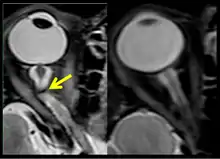

The sixth case of visual changes of an ISS astronaut was reported after return to Earth from a 6-month mission. When he noticed that his far vision was clearer through his reading glasses. A fundus examination performed 3 weeks postflight documented a grade 1 nasal optic-disc edema in the right eye only. There was no evidence of disc edema in the left eye or choroidal folds in either eye (Figure 13). MRI of the brain and eyes days postflight revealed bilateral flattening of the posterior globe, right greater than left, and a mildly distended right optic nerve sheath. There was also evidence of optic-disc edema in the right eye. A fundus examination postflight revealed a "new onset" cotton-wool spot in the left eye. This was not observed in the fundus photographs taken 3 weeks postflight.[4]

The seventh case of visual changes associated with spaceflight is significant in that it was eventually treated postflight. Approximately 2 months into the ISS mission, the astronaut reported a progressive decrease in his near and far acuity in both eyes. The ISS cabin pressure, CO2 and O2 levels were reported to be within normal operating limits and the astronaut was not exposed to any toxic substances. He never experienced losses in subjective best-corrected acuity, color vision or stereopsis. A fundus examination revealed a grade 1 bilateral optic-disc edema and choroidal folds (Figure 15).[4]